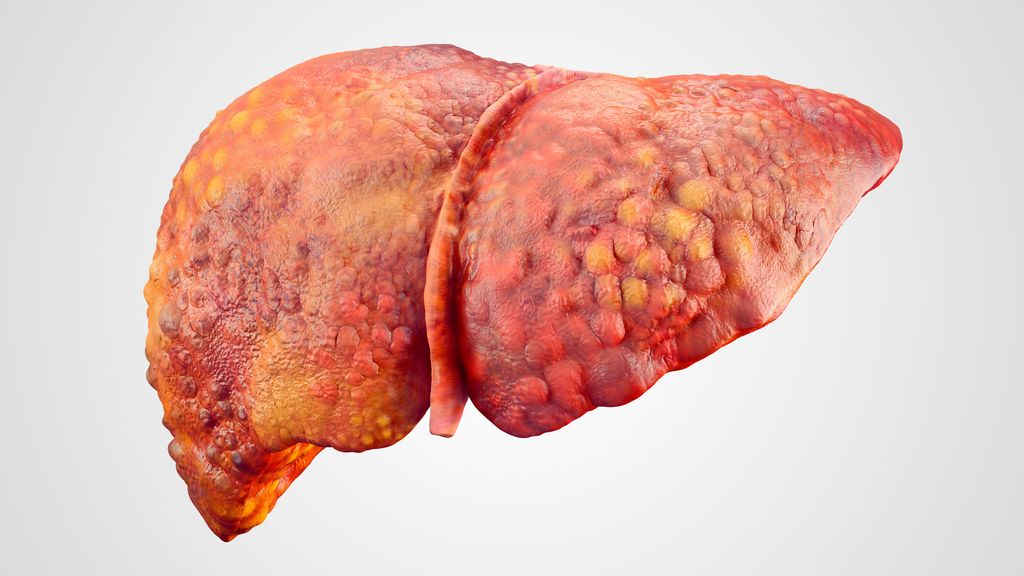

La chimiothérapie intra-artérielle constitue une extension efficace de l’éventail des traitements des tumeurs malignes hépatiques primitives et secondaires avancées. La chimiothérapie ...

Les lésions hépatiques focales sont souvent détectées lors d’examens par TDM, IRM ou échographie, non seulement en gastroentérologie et en hépatologie, mais aussi en médecine interne et ...